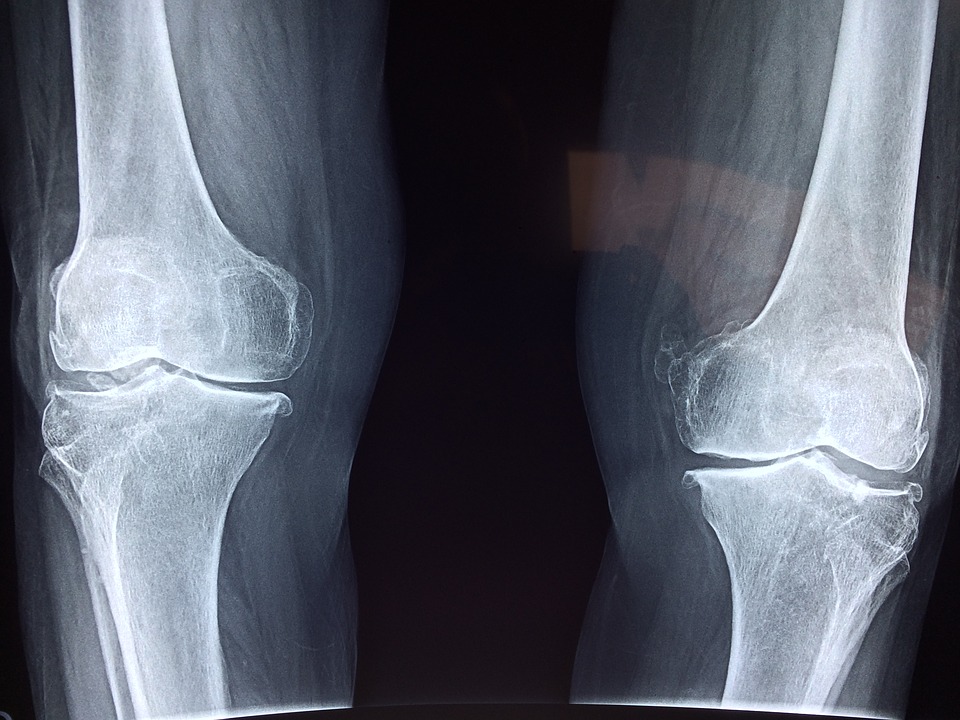

Gli Osteopati trattano molti tipi di disagi e malattie, dal mal di testa, al mal di schiena, collo e lesioni muscolo scheletriche. Tuttavia è possibile curare attraverso l’Osteopatia anche casi di asma, artrite, problemi digestivi, sindrome del tunnel carpale, colpo di frusta e problemi posturali.

Secondo l’osteopatia moderna, infatti, tutte le parti del corpo interagiscono e in particolare quando una zona del corpo è malata o bloccata, il resto del corpo deve adattarsi e compensare, producendo infiammazione, dolore e rigidità a vari livelli funzionali. In questi casi, perciò, il trattamento osteopatico aiuta a contenere il dolore, riducendo lo stress che si è andato ad accumulare nell’apparato muscolo scheletrico.

A tal fine, gli osteopati ricorrono ad una vasta gamma di trattamenti come lo stretching, il massaggio e la mobilitazione o manipolazione delle articolazioni che risvegliano la capacità naturale del corpo di ritornale all’equilibrio.